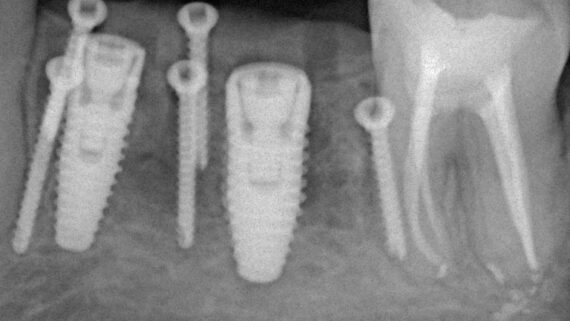

Думаю, все согласятся с тем, что последовательные хирургические вмешательства, вроде «удаление зуба — синуслифтинг — имплантация — формирователь десны» будут сопровождаться намного меньшей вероятностью осложнений, чем если бы мы провели удаление зуба, имплантацию с синуслифтингом и формированием десны за один этап. Так вот, если в случае со здоровыми людьми целесообразность подобных усложений еще можно обсуждать, то в контексте темы лечение по принципу «всё и сразу» — верный путь к пиздецу к проблемам.

Иными словами, даже в благоприятных условиях, когда, на первый взгляд, можно провести ту же немедленную имплантацию, лучше пойти наиболее консервативным путем: сначала удаление зуба, затем через 2 месяца — имплантация с закрытым ведением имплантата, затем еще через 3-4 — установка формирователя десны и протезирование.

Да, такой консервативный и осторожный подход значительно, иногда в два раза, удлиняет время стоматологической реабилитации, но тут поспешишь — людей насмешишь. Напомню, что ошибки в лечению людей на остеопорозной терапии стоят очень и очень дорого.

Третий момент имеет значение для имплантологического лечения — это грамотное и тщательное планирование предстоящих операций, в т. ч. с использованием хирургических шаблонов.

Точные и хорошо спроектированные хирургические шаблоны для имплантации позволяют не только правильно позиционировать имплантаты, тут мы и без сопливых справляемся. Намного важнее, что их использование сокращает время хирургической операции и снижает её травматичность путем уменьшения размера операционной раны. Мы не теряем время на этап позиционирования и примерок, у нас нет необходимости в большой ране — мы можем сделать разрез точно под лунку имплантата. Конечно, такие технологии хороши и для полностью здоровых пациентов, но в случае с людьми, принимающими бисфосфонаты, их использование более, чем целесообразно.

Еще раз подчеркну, что проводить имплантологическое лечение и наращивание костной ткани пациентам, принимающим бисфосфонаты МОЖНО, если осторожно. Более того, с точки зрения рисков развития осложнений, имплантация выглядит более безопасной, нежели удаление зуба. Хотя бы потому, что ушить рану при отсроченной имплантации проще, чем лунку после удаления зуба.

Ежу понятно, что в этом случае исключаются все варианты открытого ведения установленного имплантата: немедленная имплантация, немедленное протезирование, формирование десневой манжеты и т. д. Только заглушка и глухие швы после имплантации.

Вторым, уже упоминавшимся нюансом является отказ от лечения по принципу «всё и сразу» даже в ситуациях, когда это возможно:

Другими словами, если в нормальных условиях мы бы объединили синуслифтинг и имплантацию в одно хирургическое вмешательство, то в случае лечения пациентов, принимающих бисфосфонаты, лучше делать всё последовательно.

Третий пункт, — и мы про это тоже говорили, — это приоритет малотравматичных, пусть и компромиссных по результату методов лечения. Например, если в тех же нормальных условиях мы будем следовать имплантологическому правилу №2, то при лечении пациентов на антиостеопорозной терапии от него можно отступить в разумных пределах: использовать имплантаты меньших длины и диаметра, установить их в компромиссное положение и т. д.